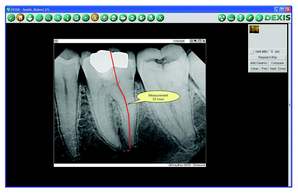

Most importantly, there’s the added benefit of better diagnostics. Sensors capture images within imaging software. This software can open up a new world for you visually with image enhancements, magnification (Fig. 2), and measuring tools (Fig. 3). There’s even implant planning that calibrates a digital image for precise 2-D measurements (Fig. 4).